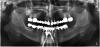

фима Опубликовано 20 октября, 2011 Поделиться Опубликовано 20 октября, 2011 Блэйд низ справа забивал в 88 году , Ну и практически за это время не видел. Теперь как обычно- хочу все и сразу - как все.По ОПГ интерпретировать патологию сложно , но готовят фото удаленных зубов- там все ясно.Выложу. Низ- убрали все , с блэйдом покувыркались , поставили все , и немедленная нагрузка.На месте блэйда сильно неудобно было , поэтому заглушил , Остался запаской. Ссылка на комментарий

фима Опубликовано 20 октября, 2011 Поделиться Опубликовано 20 октября, 2011 Через 2 -3 недели верх - выбросили все и поставил , где мог. Опять немедленная нагрузка.ОПГ сделана во время , пока делали временный.Слева планировал доставить после заживления. Ссылка на комментарий

фима Опубликовано 20 октября, 2011 Поделиться Опубликовано 20 октября, 2011 Через 7 мес постоянное протезирование. Итог- ушел один имплант неудача ,кажется вверху справа то ли 2 , то ли 3. , когда снимали временную , конструкцию, но там и так по состоянию слизистой было видно , что там проблемы . . От доставки имплантов слева после удачной времянки отказалась - для улыбания мол , хватит , пойду наслаждаться жизнью. Чувствую , опять надолго. Ссылка на комментарий

pit Опубликовано 20 октября, 2011 Поделиться Опубликовано 20 октября, 2011 Через 7 мес постоянное протезирование. Итог- ушел один имплант неудача ,кажется вверху справа то ли 2 , то ли 3. , когда снимали временную , конструкцию, но там и так по состоянию слизистой было видно , что там проблемы . . От доставки имплантов слева после удачной времянки отказалась - для улыбания мол , хватит , пойду наслаждаться жизнью. Чувствую , опять надолго.И, кстати, почему на верхней ограничились 5-ми зубами, судя по ОПГ можно было сделать закрытые синусы. Это всяко эффективнее "спящего " импланта в позиции 47-48 зуба? Ссылка на комментарий

фима Опубликовано 20 октября, 2011 Поделиться Опубликовано 20 октября, 2011 И, кстати, почему на верхней ограничились 5-ми зубами, судя по ОПГ можно было сделать закрытые синусы. Это всяко эффективнее "спящего " импланта в позиции 47-48 зуба?Справа без проблем- да , слева -нет. Первое пожелание - товарный вид. Планировалось вторым этапом синус с одномоментной доставкой имплантов справа и слева. И спокойно выходить с времянкой интеграцию в синусах.Но , к сожалению , времянка верха была слишком хороша. Ссылка на комментарий

фима Опубликовано 25 октября, 2011 Поделиться Опубликовано 25 октября, 2011 Насколько я понял в верху съемник и его не трогали, в этом и вся радость.Да вот получилось и со своими зубами вверху. Отходила с двумя времянками . ОПГ показывал выше , добавляю фото. По порядку не грузится , но, я думаю, разберетесь.Нет фото верхней времянки - мне жаль. Ссылка на комментарий